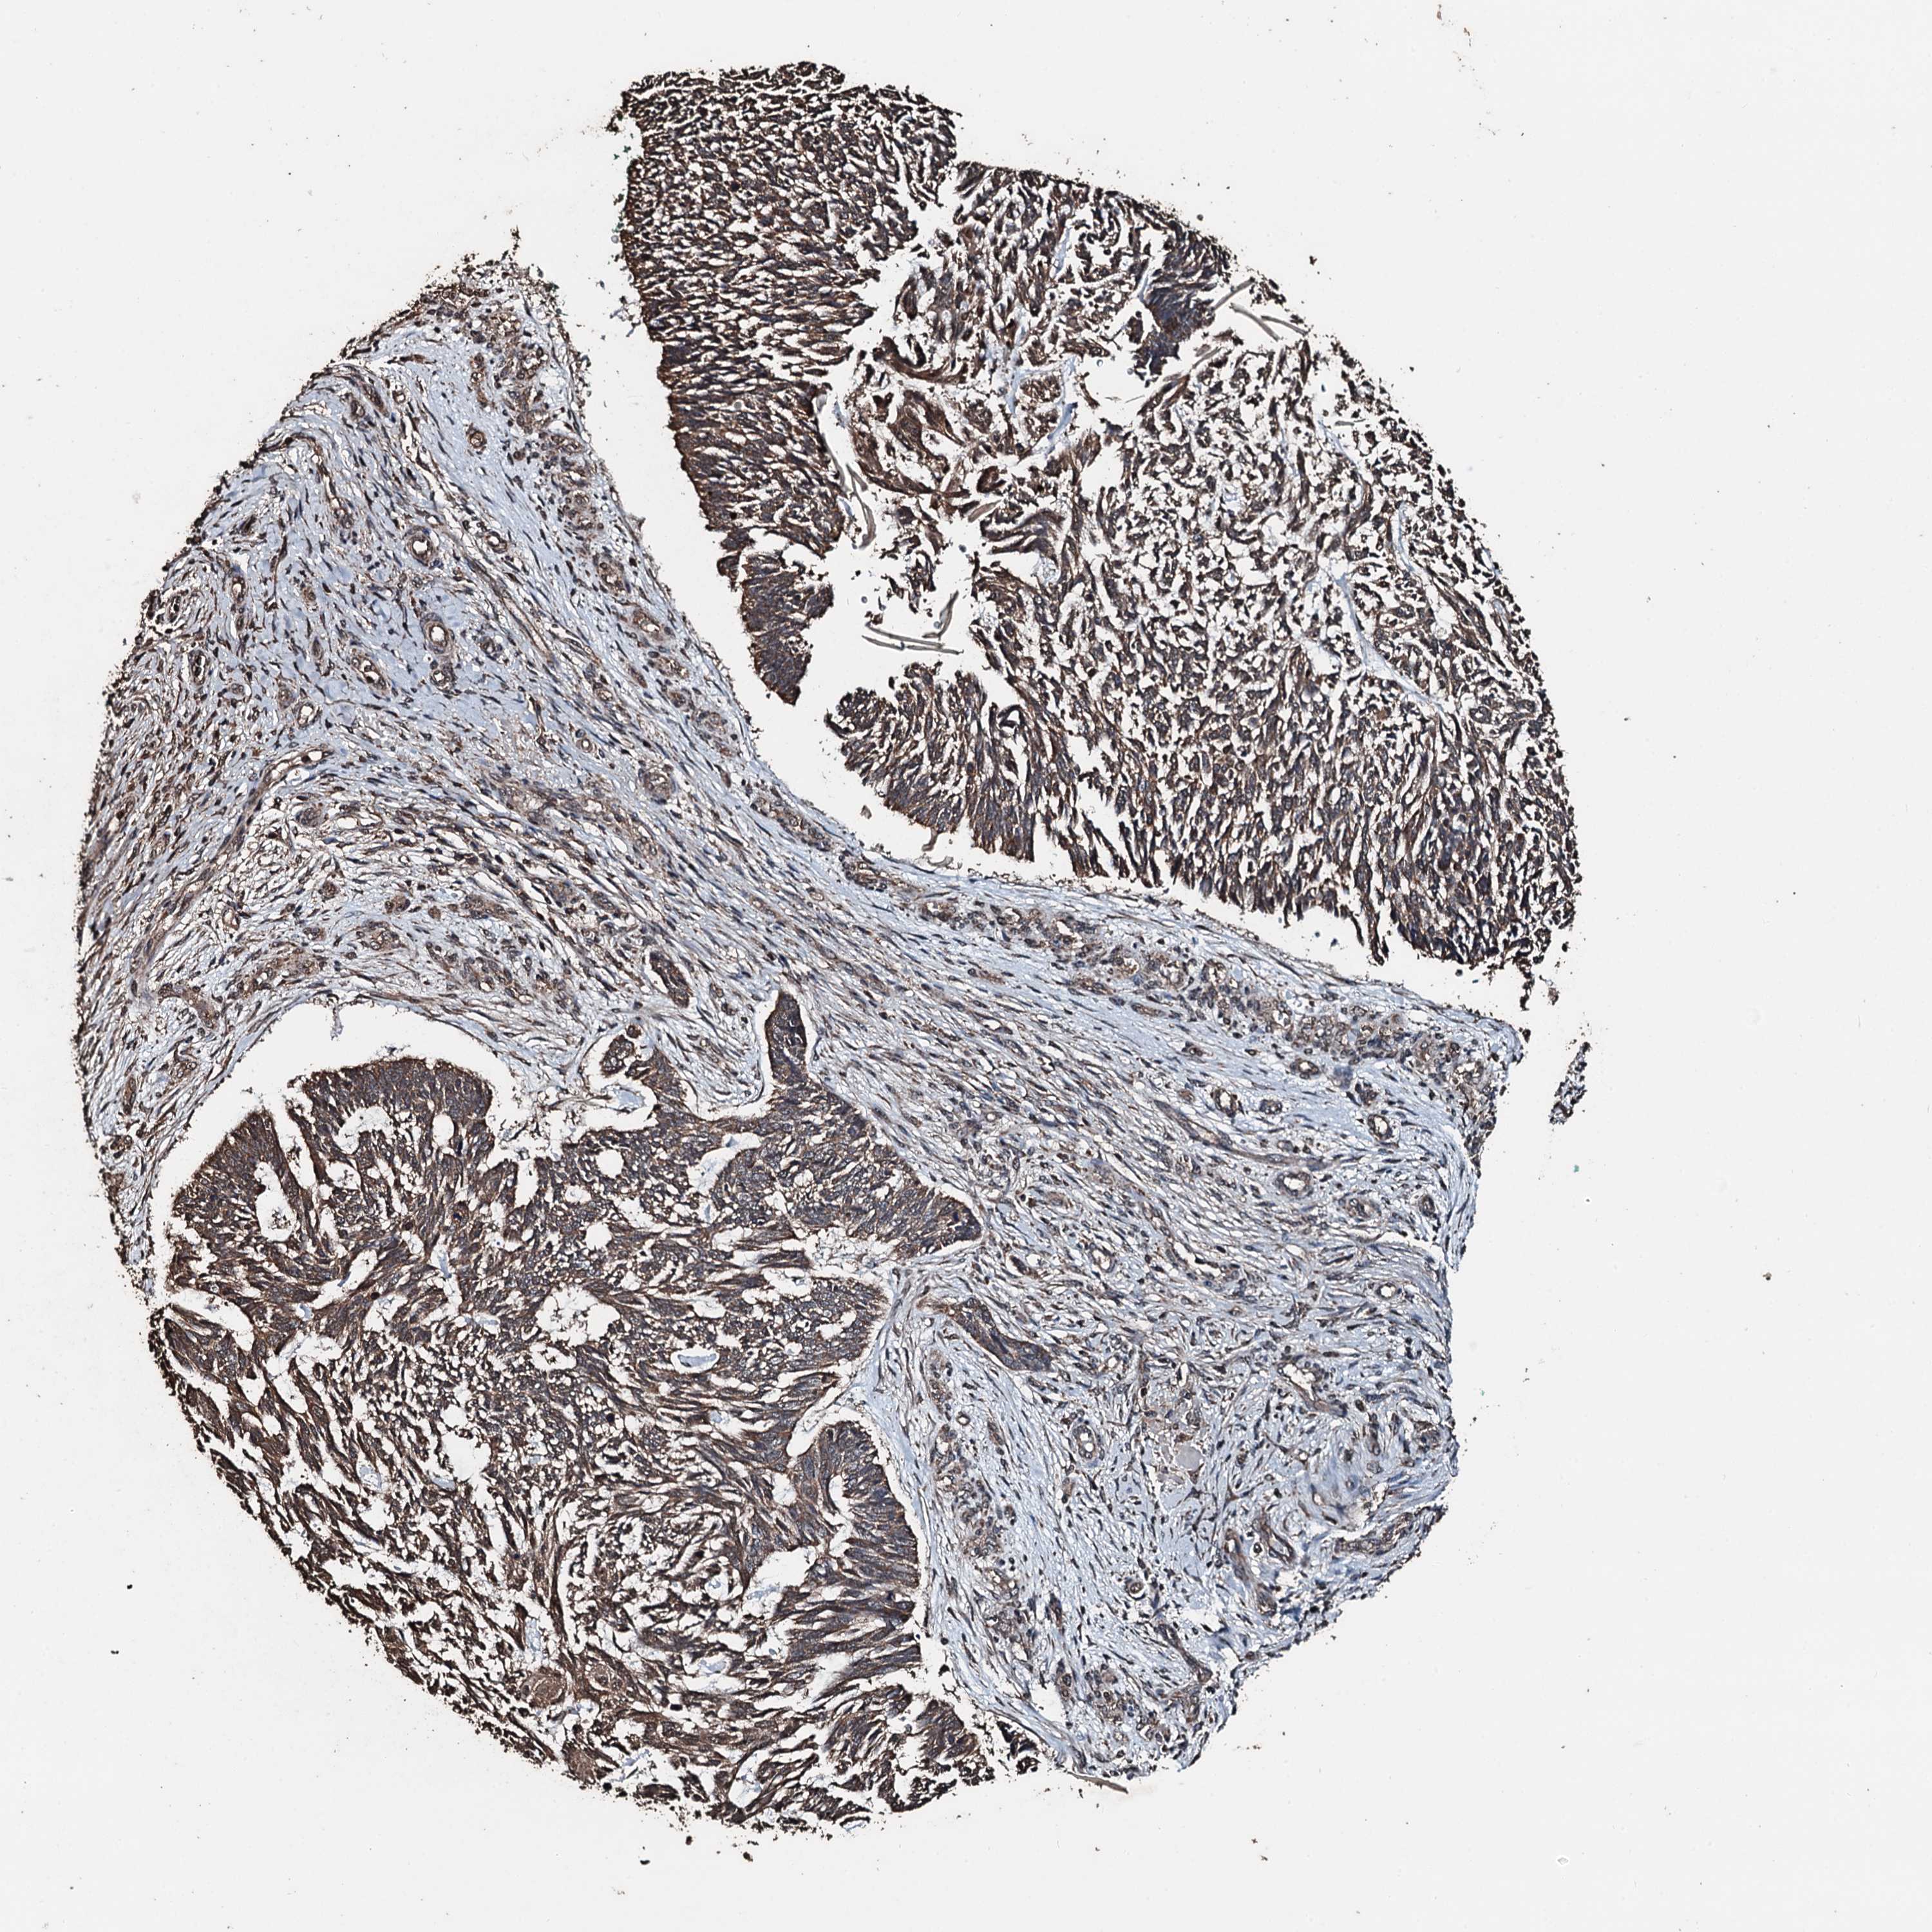

SKIN CANCER - Protein expressioni

A mouse-over function shows sample information and annotation data. Click on an image to view it in a full screen mode. Samples can be filtered based on level of antibody staining by selecting one or several of the following categories: high, medium, low and not detected. The assay and annotation is described here.

Antibody stainingi

Antibody staining in the annotated cell types in the current human tissue is reported as not detected, low, medium, or high, based on conventional immunohistochemistry profiling in selected tissues. This score is based on the combination of the staining intensity and fraction of stained cells.

Each image is clickable and will lead to virtual microscopy that enables deeper exploration of all samples and also displays staining intensity scores, fraction scores and subcellular localization as well as patient and tissue information for each sample.

Antibody HPA041168

Intensity

Strong

Moderate

>75%

75%-25%

Location

Nuclear

Cytoplasmic/membranous

Cytoplasmic/membranous,nuclear

Squamous cell carcinoma, metastatic, NOS